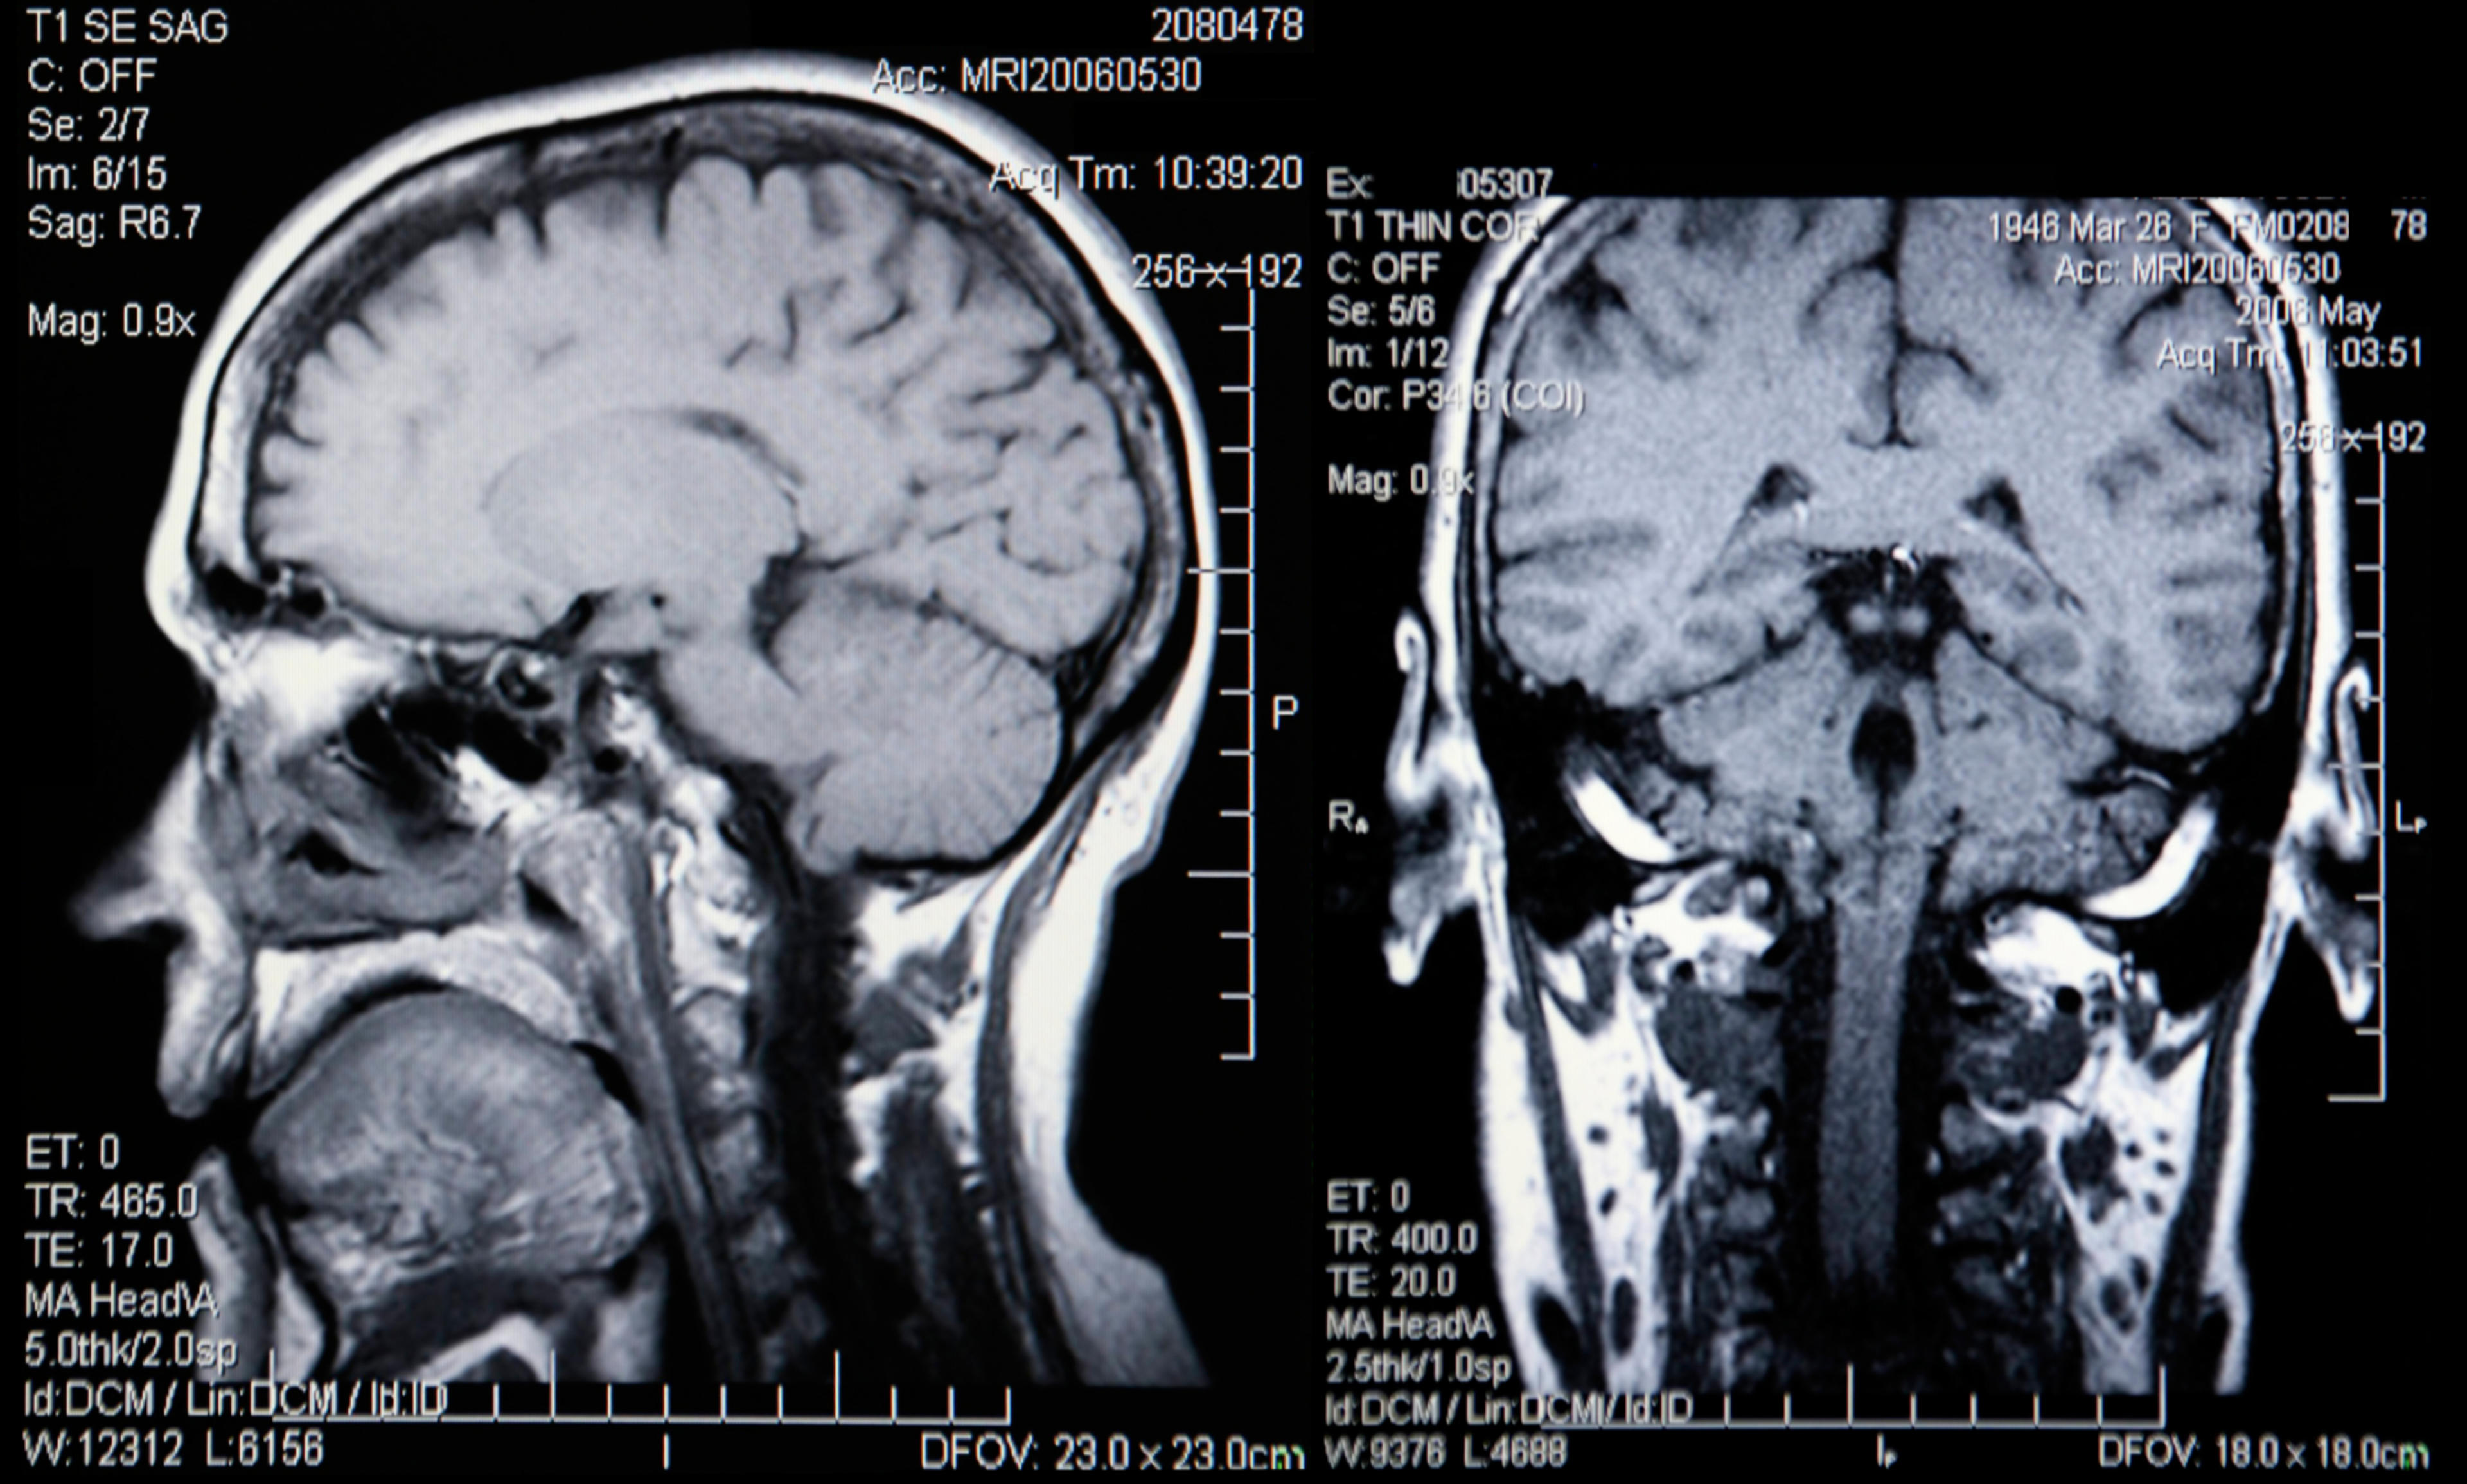

Aivojen rakennetta voidaan kuvantaa magneettikuvauksella tai tietokonetomografialla. Magneettikuvaus antaa yksityiskohtaisempaa tietoa aivorakenteesta, eikä siihen liity säderasitusta. Toisaalta tietokonetomografiallakin aivorakenteesta saadaan tarkkaa tietoa, ja se voi olla potilaalle helpompi, koska se on menetelmänä nopeampi, eikä kuvausta tehdä putkessa, vaan laite on kaarimainen. Tietokonetomografiaa käytetään myös tilanteissa, joissa magneettikuvaus ei ole mahdollinen, koska potilaalla on tiettyjä kehon sisäisiä metalliosia tai sydämentahdistin.

Kuvantamistutkimus on yksi osa diagnostiikkaa. Kuvantamisella haetaan tukea muutoin epäillylle muistisairaudelle. Lisäksi kuvantamisella poissuljetaan muistivaikeuden taustalta verenkiertoperäisiä syitä ja keskeisiä hoidettavia syitä, kuten kovakalvonalainen verenvuoto, aivonestekierron häiriintyminen ja kasvaimet.

Aivojen kuvantaminen ei yksinään riitä diagnoosiin pääsyyn, sillä aivot ovat yksilöllisiä, ja ikääntyminen sekä monet muut sairaudet voivat aiheuttaa samankaltaisia löydöksiä kuin muistisairaudet. Toisaalta etenkin sairauden alkuvaiheessa iänmukainen eli normaali kuvantamislöydös ei poissulje muistisairautta.